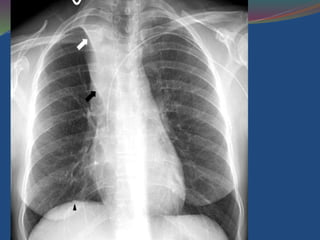

Right Upper Lobe Collapse

 Volume loss of the right upper lobe.

 Right upper zone has become dense due to lobar

collapse.

 The volume loss has displaced the trachea which

is PULLED to the right, and the horizontal fissure

(arrow) has been PULLED upwards

Right upper lobe collapse. An example of right upper lobe collapse

mimicking an apical cap of fluid (arrow).

Tight right upper lobe collapse. Note how the collapsed lobe (due to a

central bronchogenic carcinoma) results in increased right

paramediastinal density